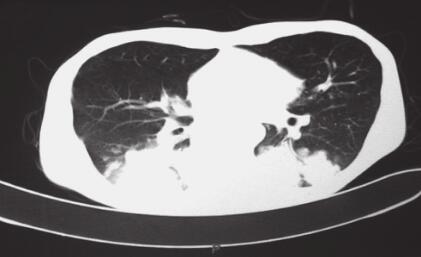

入院后检查:消瘦,双肺呼吸音减弱,未闻及干湿性啰音,无胸膜摩擦音。复查胸部CT示(图1):双下肺大片状实变影。2013年11月6日血常规示:WBC 15.02×109/L,HGB 82g/L。肝肾功能未见明显异常。入院后诊断:①肺部感染(结核?真菌?);②机化性肺炎?加用吡嗪酰胺四联抗结核,给予莫西沙星抗感染,伏立康唑抗真菌治疗。但患者仍有发热,最高体温达40℃,咳嗽、咳痰缓解不明显。于2013年11月12日在CT引导下行经皮肺穿刺术,肺组织活检病理检查结果:镜下见肺泡间隔增宽,纤维组织增生,肺泡上皮增生,肺泡腔扩张,部分腔内见胞浆空亮的泡沫状组织细胞,特殊染色示PAS(-),抗酸(-),六胺银(-)。

图1 2013年11月6日胸部CT(A.肺窗,B.纵隔窗)

双下肺斑片影,内有明显支气管充气征象,边缘可见磨砂玻璃样大小不一的结节状病灶